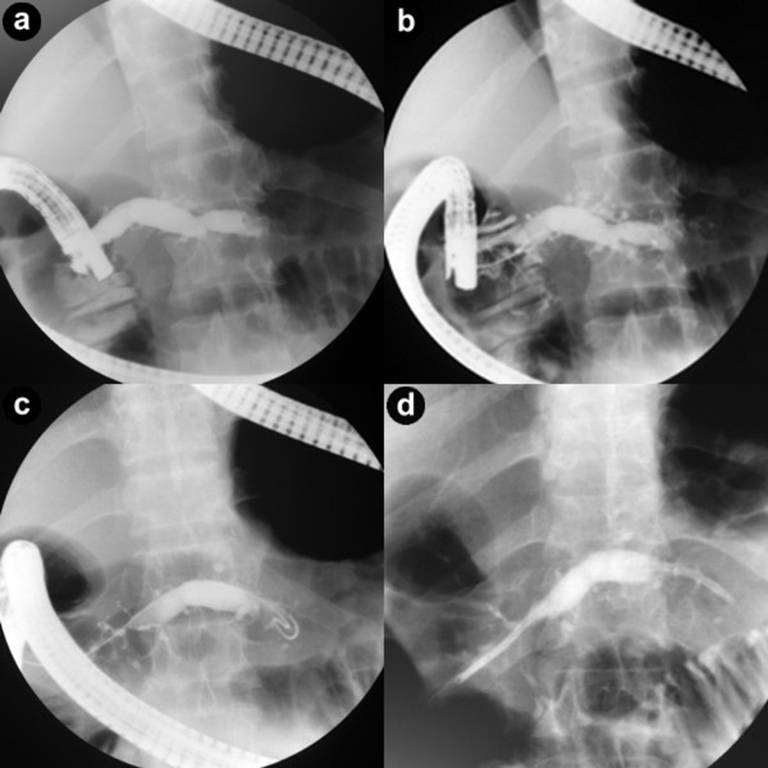

On ERCP, deep cannulation of the dorsal duct could be achieved in 47/48 (97.9%) patients and pancreatogram revealed severe and moderate ductal changes as per Cambridge classification in 25 (52.1%) and 23 (47.9%) patients respectively (Figure 1). Ductal calculi and strictures were noted in 3 (6.3%) and 2 (4.2%) patients, respectively. In one patient with ductal calculi as well as ductal stricture, deep cannulation could not be achieved and was treated surgically. In 47 patients, an endoprosthesis (5 or 7 Fr) was successfully placed in dorsal duct. In 12 patients (25.0%) a nasopancreatic drain was placed. All these patients in whom nasopancreatic drain was placed had large pseudocysts (greater than 6 cm) or pancreatic ascites/pleural effusion. Minor papillotomy was done in 7 patients (14.6%) (Figure 2) and extracorporeal shock wave lithotripsy (ESWL) in 2 patients (4.2%).

Figure 1. a. ERCP. Markedly dilated dorsal duct. b. ERCP. Deep cannulation of the dorsal duct. Markedly dilated dorsal duct with dilated side branches. c. ERCP. Guide wire negotiated into the tail end of dorsal duct. d. ERCP. Stent (7 Fr) placed in the dorsal duct. |